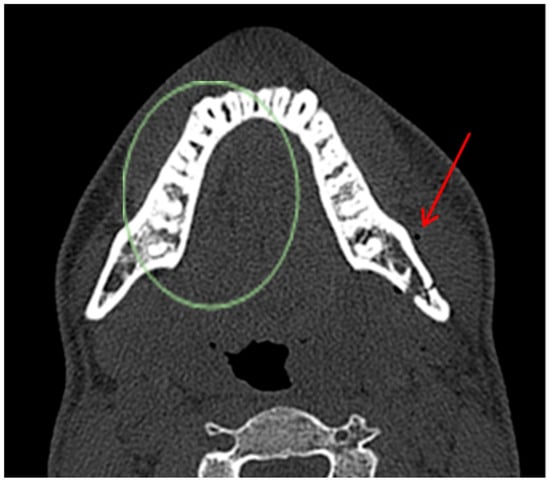

Diagnostic Utility of the “Air Sign” as a Radiological Indicator for Mandibular Body and Angle Fractures

- Open fractures: located within the body/angle of mandible;

- Closed fractures: located within the ramus, condylar/coronoid process of mandible.

- Gontarz, M.; Bargiel, J.; Gąsiorowski, K.; Marecik, T.; Szczurowski, P.; Zapała, J.; Wyszyńska-Pawelec, G. “Air Sign” in Misdiagnosed Mandibular Fractures Based on CT and CBCT Evaluation. Diagnostics 2024, 14, 362. [Google Scholar] [CrossRef]